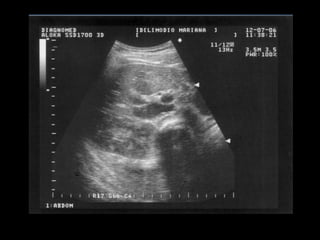

Colelitiasis

• Caracteristicas ecograficas

• Estructuras ecogénicas dentro de la luz

vesicular libre de ecos

• Sombra acustica con margenes “limpios”

• Dependencia gravitacional

• Son usualmente moviles